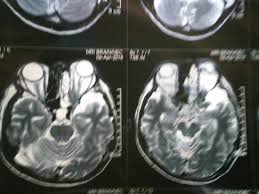

Doktor yang merawatnya mengesahkan dia mempunyai ketumbuhan di pangkal hidung, sekaligus meletakkan kanser dihidapinya di paras yang perlu diubati. İlk önce sorulması gereken ve üzerine düşünülmesi gereken konu budur aslında, kanseri ne olduğunu çeşitlerini ve tedavisi öğrenmeliyiz. Bila rujuk pakar dan buat imbasan mri ( magnetic resonance imaging ) dapat tahu dia dah hidapi kanser tahap tiga. | mhi (15 ogos 2019). Rawatan kanser npc ini bergantung kepada tahap kanser itu dijumpai. Artikel ini akan membincangkan berkenaan punca, simptom dan rawatan kanser tekak. Hidung jadi senget, sekarang dah merebak ke mulut. Sungguhpun disahkan menghidap kanser esofagus tahap empat, pelakon zaibo masih mampu tersenyum ceria melayan. 30, yang menderita kanser limfoma tahap empat. Tidak dapat dipastikan kanser apa yang dihidapi elyana ktika ini. Arwah sebelum ini disahkan menghidap kanser esofagos beberapa bulan lalu pada tahap empat dan tidak boleh menelan makanan ketika bulan puasa tahun ini. Kanser tahap 4 sering digelar sebagai kanser tahap akhir. Terkini, pada hari jumaat yang mulia, wanita ini 'pergi' menghadap illahi.

Siapa sangka kisah isteri cekal hatinya sanggup berjuang meneruskan hidup setelah dia menghidap kanser payudara tahap 4. Elyana atau nama sebenarnya erneelya elyana emrizal membuat pengakuan tersebut secara terbuka selepas diumumkan tersingkir di konsert minggu kelima gv 4 pada malam. Masa pergi klinik kesihatan berlaku pendarahan hidung. Bila rujuk pakar dan buat imbasan mri ( magnetic resonance imaging ) dapat tahu dia dah hidapi kanser tahap tiga. Hastalık, hücrelerin kontrolsüz çoğalması ve normal hücrelere yer bırakmaması ile başlar.